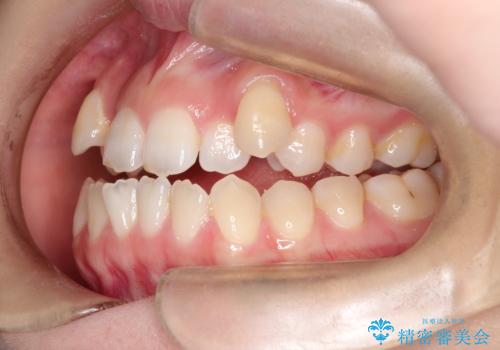

MARPEで非抜歯矯正|オープンバイトと八重歯を改善

- 治療計画

上顎にTAD(矯正用アンカースクリュー)を設置し、MARPEにより骨格レベルで上顎の幅を拡大。数週間の拡大期間を経て十分なスペースを確保したのち、マウスピース型矯正装置(インビザライン)で歯列全体を整えました。八重歯もアーチ内に自然に収まり、非抜歯で審美性と機能性を両立。治療後は「噛み合わせが安定して笑顔に自信が持てるようになった」とご本人にも大変満足していただきました。